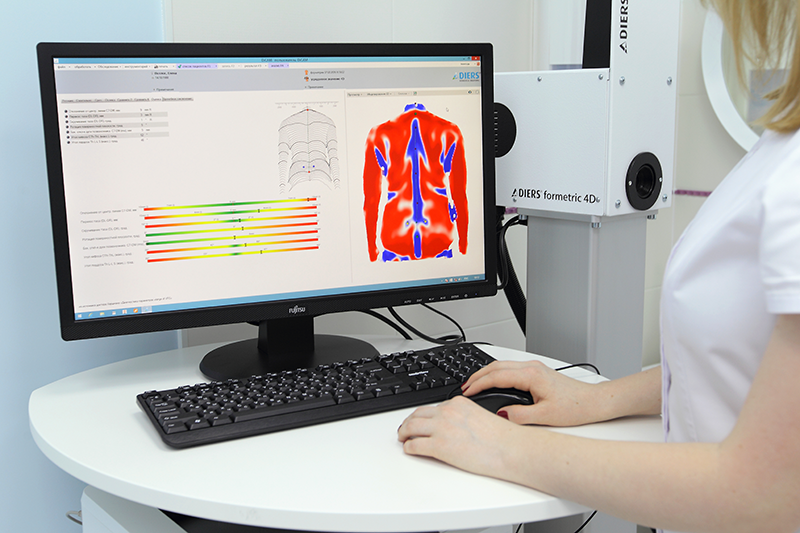

Оптическая диагностика позвоночника Diers: изображения и технологии

Раздел: Мир в картинках